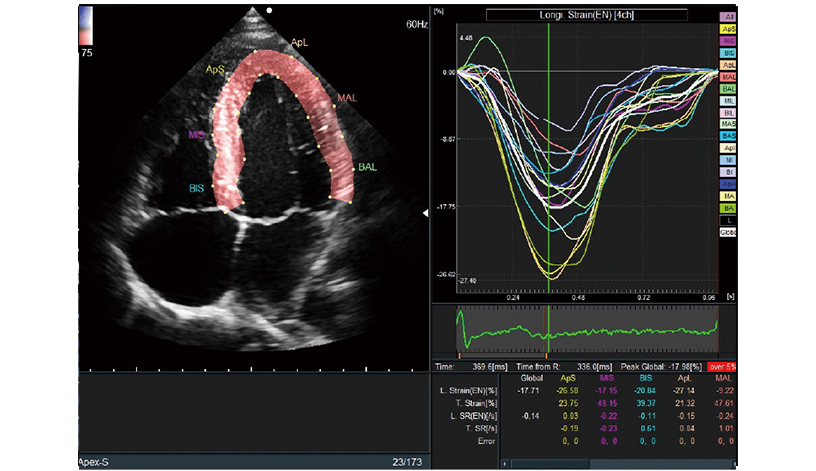

Conducts various measurements via the 2D tracking method fully automatically using AI Technology*1. One of them, Global Longitudinal Strain (GLS), is attracting attention in heart failure examinations.